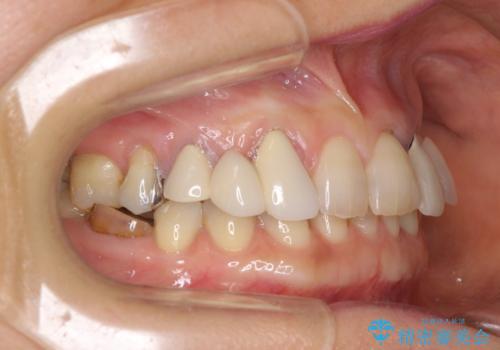

左上の歯は割れてしまっており、抜歯のうえインプラント治療が必要であり、他にも抜歯の必要な歯がある状態でした。

上顎はほぼ全ての歯をセラミッククラウンにて補綴治療を行う必要があるため、気になるデコボコや深い咬み合わせを改善するために下顎と上顎の臼歯部の矯正治療を行うこととしました。

並行して左下にはインプラントを埋入し、矯正治療を終えると同時に補綴治療を行うこととしました。

過蓋咬合(下顎前歯が隠れてしまうほどの深い咬み合わせ)のため、スムーズに歯が動かず矯正治療に時間がかかりましたが、無事に仕上げることができました。